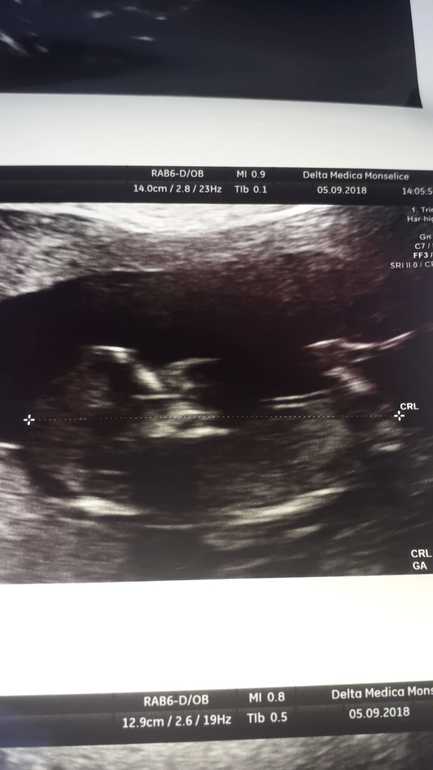

Я вижу девочку. У меня тоже девуля и по фото УЗИ похоже у вас тоже куколка. Смотреть на белую палочку справа на фото . Если она паралельно позвоночнику-девочка, если под углом 30°- мальчик. А вообще главное,чтоб был ребеночек здоровенький!!!

Как там можно увидеть что-то между ног, если видно только одну ногу. И бугорка не видно, не тот ракурс((

11.09.2018

Согласна, не тот ракурс. Но все же, когда первый раз увидела, почему то показалась девочка. Сама не пойму почему. Посмотрим.

Подруга послала фото сегодня. Это я так, просто для интереса. Знаю, что качество не очень. Но мне кажется девочка.

Нет, я всерьёз не воспринимаю. Это фото неудачное, конечно. Знаю, что на ББ девочки глазастые, они даже тесты рассматривают. Это просто так, моей подруге все равно мальчик, или девочка, это у неё 5 ребёнок. Не судите уж так строго. 🤭☺️